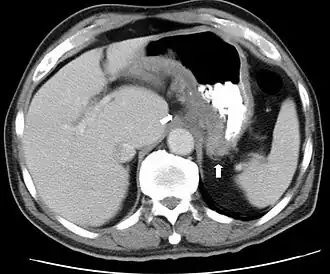

Durch Computertomographie (CT) gewonnenes Schnittbild einer axialen Schichtung – die dargestellte Transversalebene des menschlichen Oberbauchs entspricht der Lage der grünen Ebene in der Abbildung oben

Bei den bildgebenden Verfahren der Radiologie – insbesondere den anhand der Untersuchungsdaten errechneten Darstellungen von Körperquerschnitten bestimmter Schichtdicke (Tomographie) – spielen Transversalschnitte eine wichtige Rolle. Sie stellen die aufgenommenen Bilddaten in verschiedenen Transversalebenen dar, die mit bestimmten Abständen längs der Körperachse aufeinander folgen und so in axialer Schichtung ein Bild des Körpers geben. Bei der tomographischen Untersuchung wird eine Serie transaxialer Schnittbilder erstellt, die den untersuchten Körper Schicht für Schicht transversal darstellen.[1]